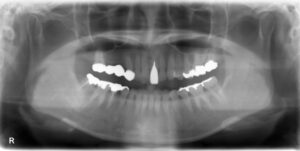

下顎大臼歯1本欠損症例

BEFORE AFTER 53歳女性/下1本欠損/インプラント埋込手術 【治療内容】 歯根の先で炎症が広がり、抜歯となっ…